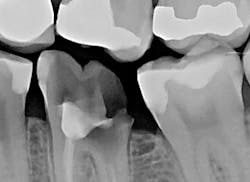

The patient presented with tooth No.19 ML with a history of endodontic treatment fractured to the level of the alveolus (figures 6-8). The patient had an inadequate clinical crown to restore. The options were either to extract the tooth and place an implant, or complete a crown lengthening and then restore. The clinical objective of crown lengthening was to establish biologic width and expose enough tooth structure coronal to the bone for a proper restoration. The patient opted for crown lengthening, and the procedure was completed in about 50 minutes.

Figure 6: Pre-op

Figure 7: Pre-op

Figure 8: Pre-op

With traditional instruments, this procedure is typically completed with a scalpel and high-speed handpiece with burs. A larger flap is required to improve visibility and instrumentation. However, with Solea's precision and small spot-size options, a much smaller flap was needed. There was less bleeding, resulting in a cleaner surgical site and faster postoperative healing. As the radiograph and photos show, excellent conditions for the final restoration were established. The final crown demonstrated sound margins and evidence of proper biologic width. As the five-day follow-up photo shows, the healing time was fast, and tissues appear healthy.